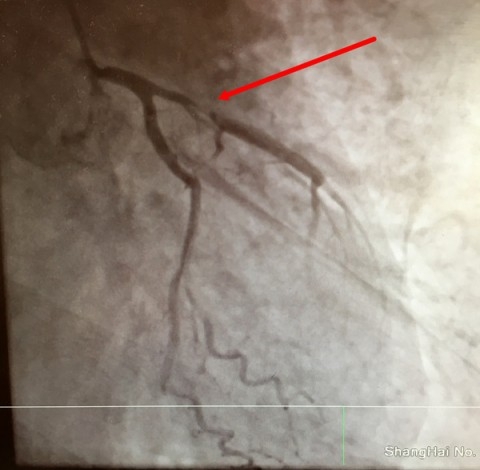

中午12时,持续抢救四小时,患者室颤发作次数有所减少,机不可失,抓住短暂平稳间期立刻手术开通血管,是患者生存唯一可能。徐迎佳主任亲自护送,立刻携带呼吸机、除颤仪、监护仪等设备将黄先生安全迅速转运至放射科介入导管室,风驰电掣展开心脏冠脉造影手术。术中,黄先生再次室颤,又一次抢救除颤复律成功。徐迎佳主任与张高峰主任医师、乔琪主治医师等抓住稍纵即逝的机会,冠脉造影显示前降支近端闭塞,迅速置入支架,手术仅用了20余分钟。